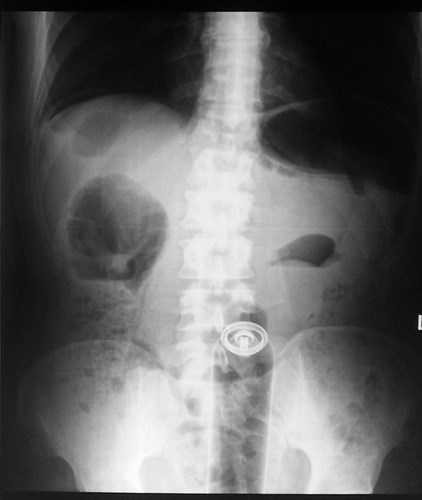

| Một tên buôn lậu tại Luân Đôn, Anh đã liều mình nuốt trọn 67 túi cocaine, với khối lượng khá lớn vào dạ dày của mình, để dễ dàng vận chuyển và hòng qua mặt cảnh sát. Nhưng thật không may, tên này đã bị bắt giữ, nhưng trước khi bị giải về đồn cảnh sát, hắn đã phải vào bệnh viện để lấy 67 túi cocaine ra ngoài. |